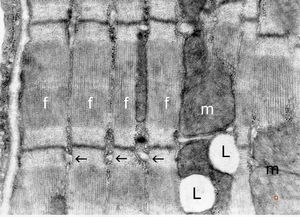

normal cardiomyocyte … longitudinal section(m … mitochondrion, f - myofilaments, L … lipid droplets, arrows … tubulesof sarcoplasmic reticulum)